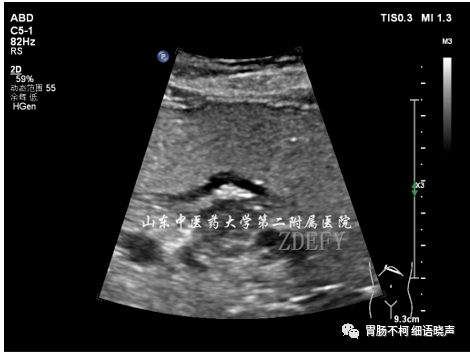

病例三,胃体偏后壁胃壁增厚性病变,层次尚清晰,黏膜面浅溃疡形成: